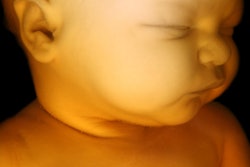

Coronal slices of MRI (left), PET (center), and fused PET/MRI (right) of a woman at 18 weeks of pregnancy. Of particular interest is the level of uptake in the fetal organs. While the heart showed high F-18 FDG uptake, the brain had only a low level of glucose consumption, especially compared with brain uptake of the mother. This pattern of low glucose consumption has previously been noted even in mature fetuses. All images courtesy of the Journal of Nuclear Medicine.Cervical and ovarian cancers are the most common gynecological cancers diagnosed during pregnancy, and malignancy during pregnancy is increasing, according to the authors. Studies show the most common type of malignancy is uterine cervical cancer.

All fetuses were visible in detail on the MRI scans, which allowed the delineation of their body contours. F-18 FDG activity was unevenly distributed in the fetal body. The hearts were generally visible, while the brain showed low uptake, the results showed.